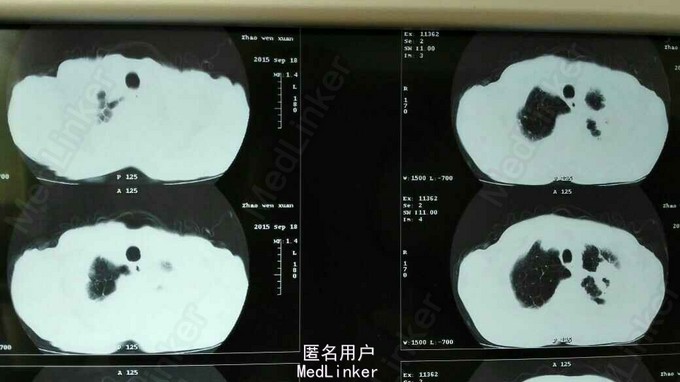

TPR:38.0 80 20,血压130/80mmHg。左肺下叶叩诊呈浊音,听诊呼吸音低,双肺可闻及少许湿胸罗音,未闻及喘鸣音。心脏及腹部查体未见明显异常。 辅助检查见图。

继发性肺结核 左侧 涂阳 初治 尿毒症 原发性高血压3级 极高危 治疗方案:2HRZE/4HR

讨论:形成肺部空洞原因有很多。看看下面的资料,您还会确认此患者的空洞是单一因素吗?我们现在给患者规律抗结核治疗,随访影像学变化。 尿毒症合并肺结核我们的治疗经验减少,密切观察药物相关副作用。 【病因机制】 (一)病因分类 (1)肺部感染性疾病:如肺结核空洞、肺脓肿、肺曲菌病。 (2)肺肿瘤性疾病;如肺癌性空洞、肺转移瘤空洞、淋巴瘤空洞。 (3)肺梗死。 (4)硅沉着病。 (5)结缔组织病及风湿性疾病:如类风湿肺病、韦格纳肉芽肿。 (二)发病机制 各种不同的病因引起肺实质坏死、液化,坏死物经支气管排出,空气进入而形成环形阴影,不同疾病发生空洞的机制各不相同,下面讨论几种常见疾病的发生机制。 (1)肺结核空洞:肺结核是由于人型或牛型结核杆菌或非洲型分枝杆菌引起的肺部慢性感染性疾病。肺结核基本病理变化为炎性渗出、增生和干酪样坏死。结核病的病理过程特点是破坏与修复同时进行。渗出为主的病变主要表现在结核炎症初级阶段或病变恶化复发时,肺组织充血、水肿、并有大量中性粒细胞浸润,继之由巨噬细胞及淋巴细胞取代。增生为主的病变表现为典型的结核结节,中间可出现干酪坏死。干酪坏死为主的病变多发生在结核分枝杆菌毒力强、数量多、机体超敏反应增强,抵抗力低下,以及没有有效的治疗或治疗不彻底,渗出性病变进一步发展,此阶段肺组织自溶并逐渐向干酪性坏死转化。干酪性坏死肺组织液化,病灶破溃入支气管。进入空气即形成结核性空洞。液化组织中有大量的结核菌可沿支气管播散并以飞洙方式成为结核病的传染源。结核性空洞形成后,空洞壁周围以纤维结缔组织增生来修补,逐渐形成管壁增厚的偏心空洞,空洞周围可见增殖为主的纤维播散病灶和结缔组织。 (2)肺脓肿:肺脓肿所致空洞是指肺部细菌化脓性炎症,肺组织坏死液化,脓液经支气管引流后,形成的肺空洞。肺脓肿的发病机制与病因密切相关,根据病因及感染途径分为三种: 1)吸入性:吸入物包括副鼻窦炎、扁桃体炎、牙周病所致脓性分泌物;口、鼻咽部手术后血凝块;全身麻醉或神志昏迷病人呕吐物、齿垢甚至假牙;免疫功能低下和体弱多病的老年病人吸入含细菌的口腔分泌物等,使细支气管阻塞,细菌繁殖或原虫直接侵犯,导致局部肺组织炎症,继之肺小血管栓塞,肺组织缺血发生变性、化脓、坏死,最终形成肺脓肿。肺脓肿及周围肺组织由于缺血、缺氧,常合并厌氧菌感染.可加重组织坏死。由于脓腔内压力增高,液化的脓液可破溃至支气管内而咳出大量脓痰,空气随之进人脓腔,从而形成空洞。由于脓液排出不完全,空洞内多形成液平。应当注意,位于边缘部的脓性空洞可破溃至胸膜腔,并发脓气胸。 2)血源性;常因继发于皮肤创伤、感染、疖痈、亚急性细菌性心内膜炎、脓毒症,以及菌栓血行播散到肺,引起小血管栓塞、炎症和坏死而形成肺脓肿。 3)继发性:继发性肺脓肿常继发于其他肺病包括肺炎(主要为金黄色葡萄球菌性肺炎菌和肺炎杆菌性肺炎)、空洞性肺结核、支气管扩张、支气管肺癌和支气管囊肿等,继发感染导致继发性肺脓肿。或邻近器官直接蔓延。如内胸壁感染、膈下感染或肝脓肿等直接蔓延累及肺。无论哪种感染途径,肺组织均发生炎症、坏死、液化,经支气管排出后形成空洞。 (3)肺癌空洞:空洞型肺癌指肺癌瘤体内产生空洞而言,肺癌内出现空洞可能的机制有以下三种:①肿瘤的供血动脉发生栓塞、致癌缺血、坏死、液化、液化后空洞与支气管相通、坏死物质经支气管咳出形成空洞。②某些肺癌细胞能分泌蛋白溶解和脂肪溶解酶,这些酶可以使肿瘤组织液化、排山;③癌组织中可能会有分化良好的汗腺、皮脂腺,这些腺体的分泌物经支气管排出后而形成。空洞型肺癌占全部肺癌的6%~16%,以鳞癌发病率最高,约占80%,其次为腺癌、大细胞癌、最少见为小细胞癌。 (4)曲菌性肺空洞:肺真菌感染,目前以念珠菌、曲菌、组织胞浆苗为最常见,均为条件致病菌,只有为病人免疫功能低下才入侵肺部而发病。肺曲菌病主要为烟曲菌的丝状曲菌感染所致。曲菌球多继发于肺结核空洞,支气管囊状扩张,偶可见癌性空洞。曲菌寄生于肺部慢性坏死性病灶的空腔内,丝状体在原发病的空腔内的破坏组织中大量繁殖,聚集在空腔内与纤维蛋白和黏膜细胞及细胞碎屑凝聚构成曲菌球。球体周围仍为空腔即形成曲菌性肺空洞。一般情况下,曲菌球较少侵犯周围肺组织。